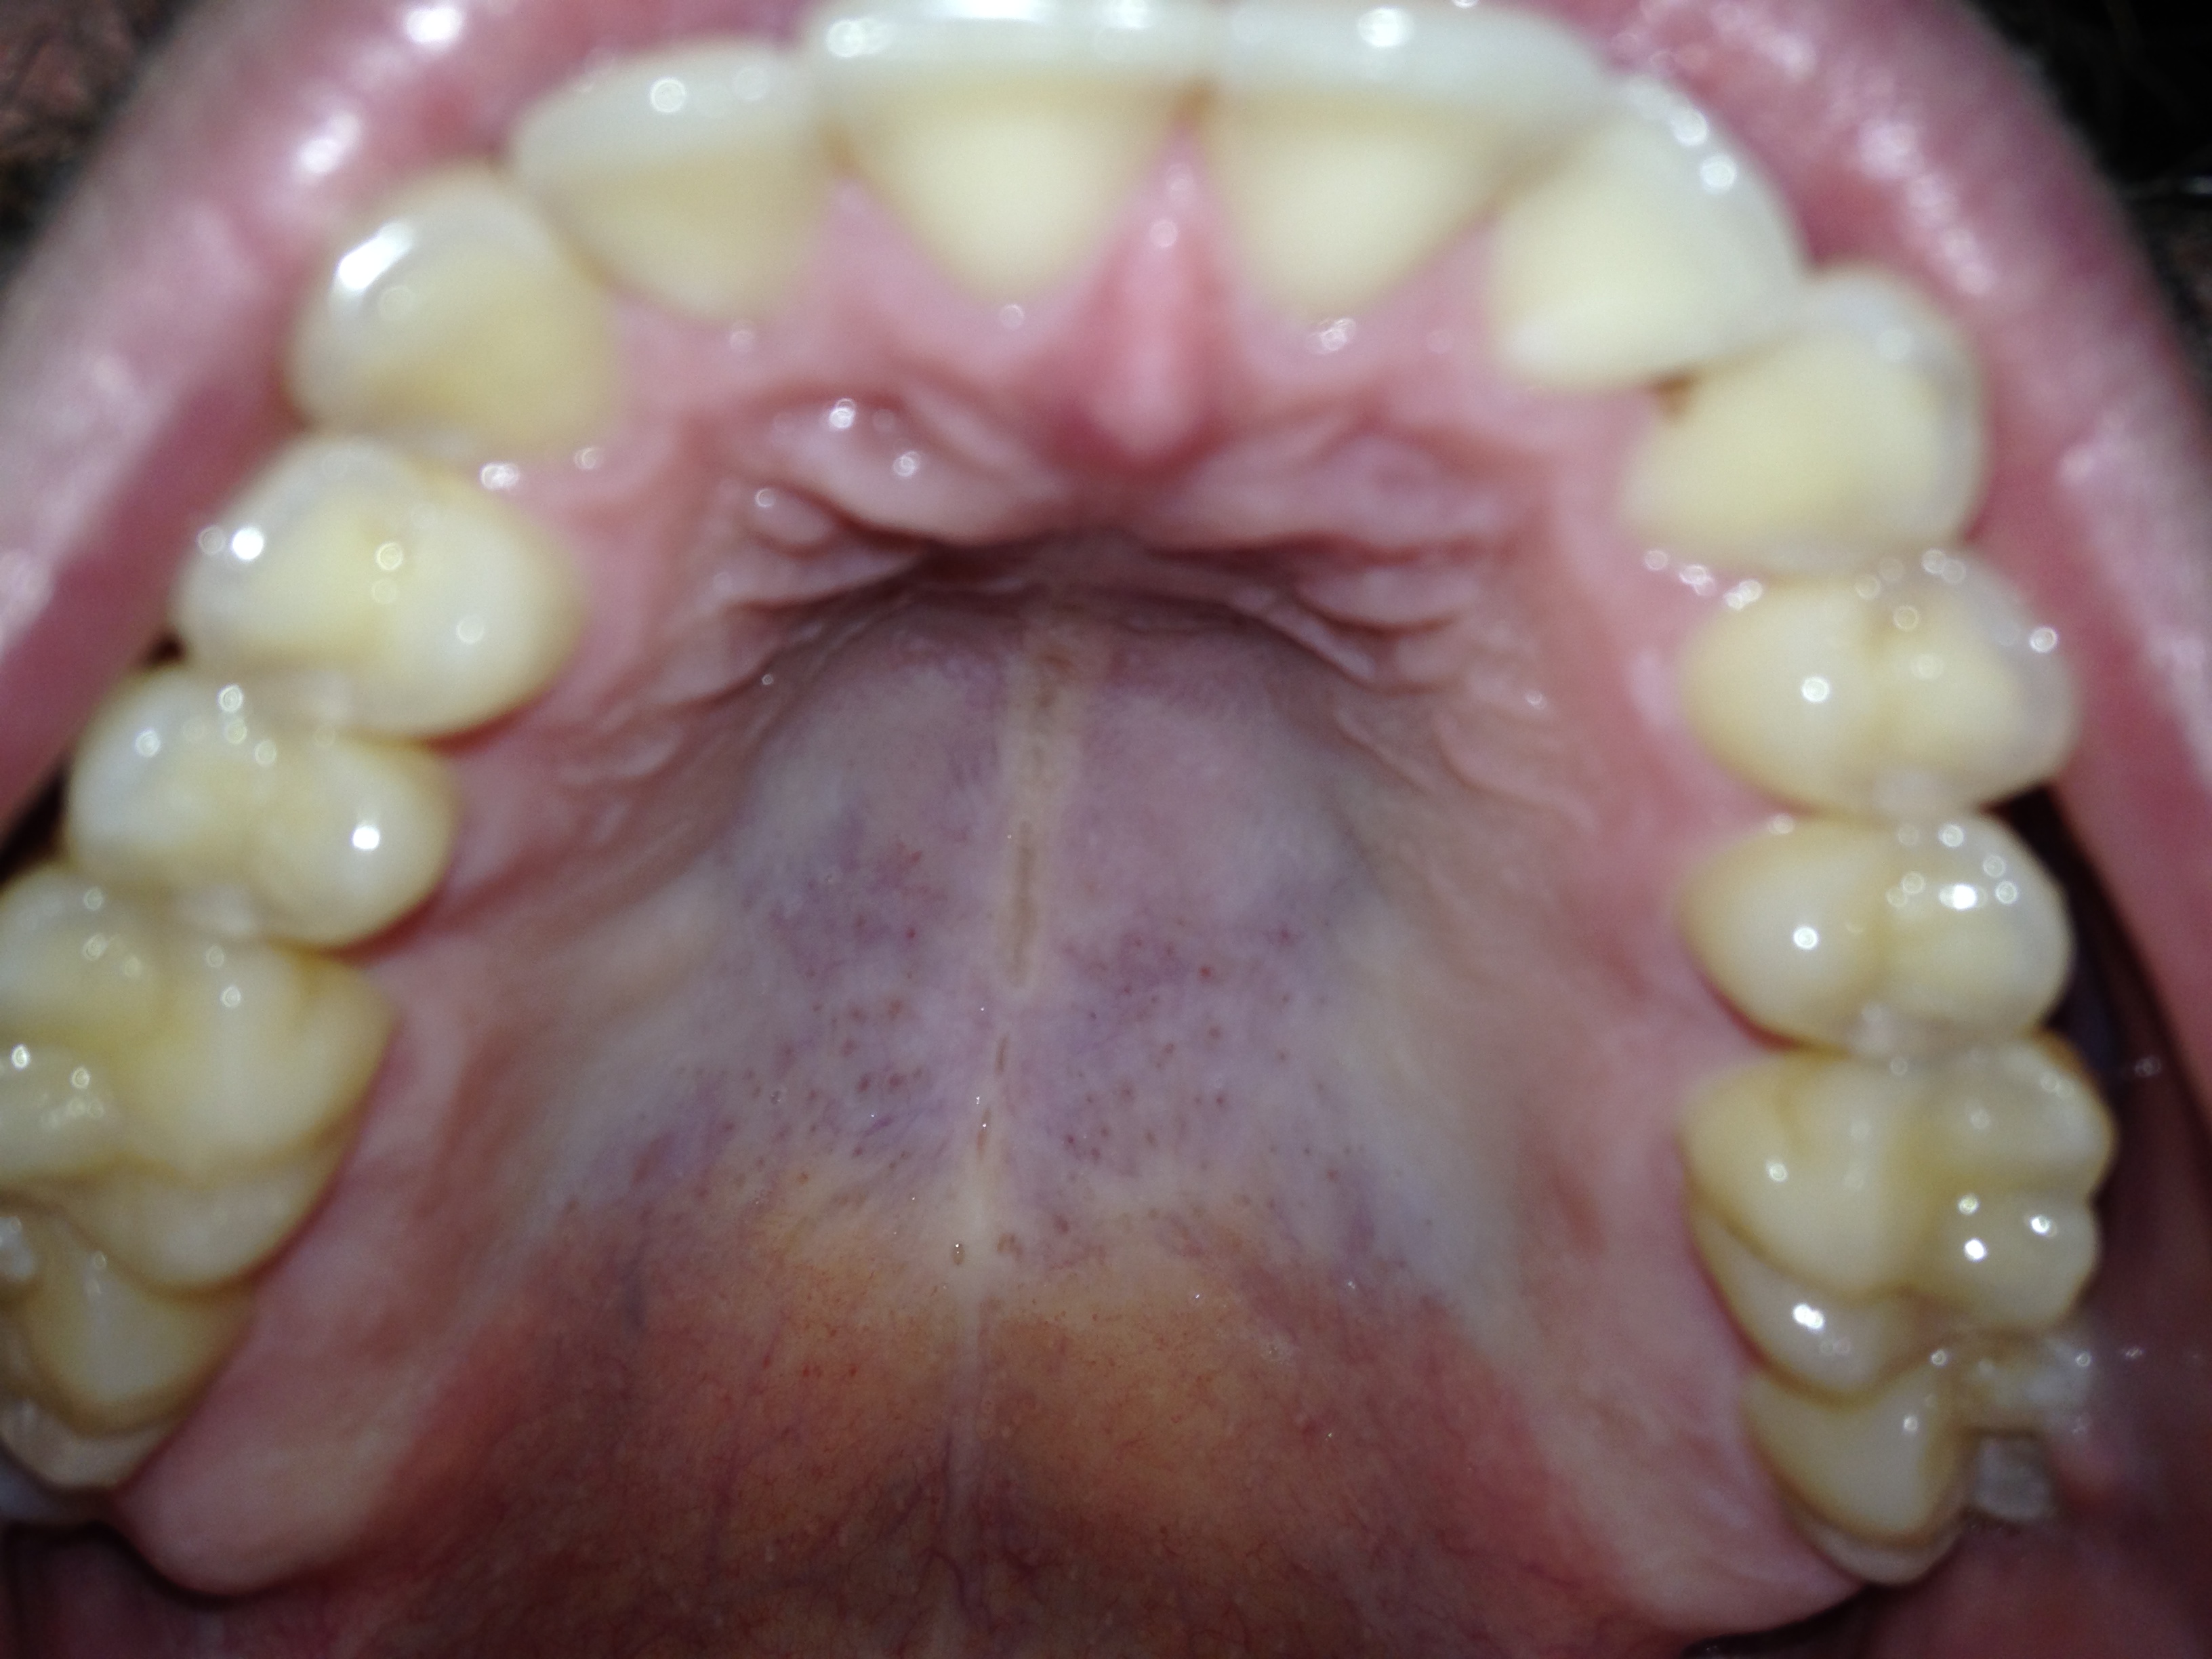

Ik zie dat de randen van mijn tanden en kiezen best doorzichtig zijn en las dat dit tanderosie kan zijn, daarnaast zie ik de dentine. Ik nuttig geen suikers of zuren dus ik begrijp niet waarom ik dit zou hebben. Daarnaast heeft de tandarts er nooit wat over gezegd. De eerste foto is van vandaag, de andere van 2015 (foto's van de boventanden). Als ik deze twee foto's vergelijk zie ik dat er geen verschil is en dat bij beide foto's evenveel doorzichtigheid en dentine te zien is.

De tweede foto v d bovenkaak is niet duidelijk en voor de onderkaak is geen tweede vergelijking. Hoe is de PH v uw speeksel, wat eet u ...v zoveel factoren afhankelijk. Enige wat ik zie is dat u vrij doorzichtige tanden/kiezen heeft Dat hoeft niet negatief te zijn.

De tweede foto is inderdaad niet heel scherp, maar als je goed kijkt zie je dezelfde doorzichtigheid (heb een foto met pijltjes toegevoegd). Ik eet best gezond en mondhygiëne is ook best goed, ik vermijd suikers en drink voornamelijk water. Geen idee wat de PH is helaas, vind het ook apart dat mijn tandarts er nooit wat over heeft gezegd.

Hierbij 3 foto's van mijn onderkaak. De eerste foto is van mijn linker onderkaak van 2017, de tweede foto is van mijn rechter onderkaak van 2017 en de laatste foto is van 2015 van mijn gehele onderkaak. De foto van 2015 is met een andere telefoon genomen, hierdoor is de kleur en belichting wat anders, echter zie ik bij alle drie de foto's en de foto van 2025 de zelfde hoeveelheid doorzichtigheid.